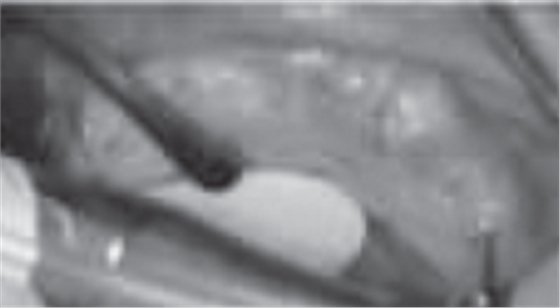

根據所得信息將制定16、13、23及26為種植體位置行all-on-4種植手術。種植手術:常規(guī)消毒、鋪巾,甲哌鹽酸阿替卡因局部浸潤局麻下,患者戴上去除牙膠并已消毒后的放射模板,在16、13、23及26位置用球鉆定位(圖9、10、11、12),行微創(chuàng)切口(圖13),從17至12和從27至22的切口,并在所定位置逐級備洞,分別在13、16、23及26各植入一枚Nobel Replace Conical Connection 4.3mm*13mm種植體,同時在13、23接30°復合基臺,在16、26接復合直基臺(圖14)。嚴密縫合后行即刻修復(圖15、16、17、18)。

圖13 定位后行微創(chuàng)切口